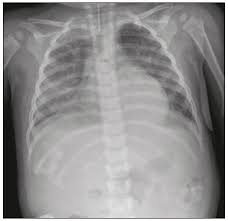

Radiologia Brasileira Achados Iniciais Na Radiografia De Torax Em Uma Populacao Pediatrica Com Diagnostico De Infeccao Viral Por H1n1